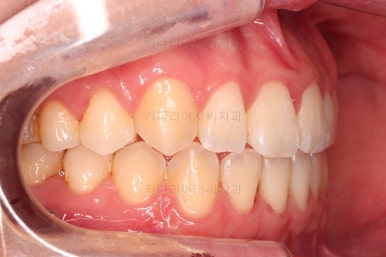

1. 처음 내원 시의 입안의 모습

부산치아교정잘하는곳 키다리아저씨치과에 처음 내원하셨을 당시의 입안 모습입니다.

얼핏 보면 많이 삐뚤어지지는 않은 편인데, 눈에 바로 띄는 앞니가 뻗쳐 있으면서 획 돌아있는데요. 정렬이 필요한 상황이었습니다.

어금니쪽은 많이 삐뚠 편은 아니었으며, 윗니 앞니가 많이 앞으로 뻗쳐 있는 상태였습니다.